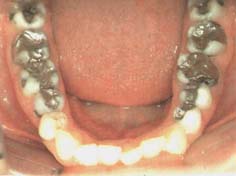

Amalgamgebiss mit Amalgam in Backenzähnen [1]

Amalgamgebiss

mit

Frontzähnen aus Amalgam [2]